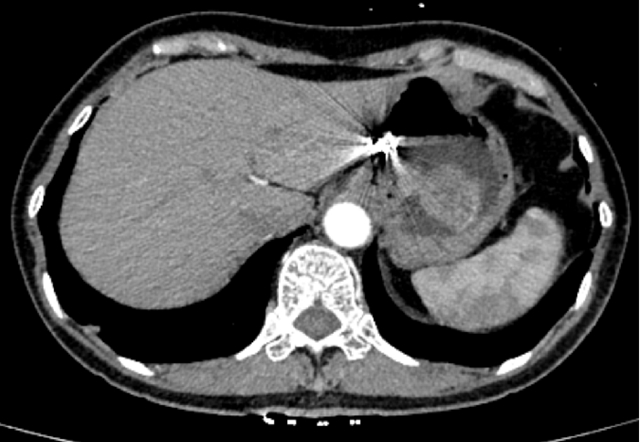

1月后复查CT与胃镜,患者瘤体有明显缩小,并且供血的主要动脉血管已经完全被栓塞。

CT检查提示体内的胃黏膜下肿瘤有所缩小,意味着栓塞成功。而后,汤小伟副教授为李婆婆进行内镜下ESD切除术。他带领团队在患者胃黏膜表面开一个小口,内镜经由这个小口在黏膜下层建“隧道”直至肿瘤位置,再将肿瘤和周边组织分离后切除取出。50分钟左右,手术顺利完成。最终的病理结果提示肿物的性质为胃间质瘤(低危险度),属于预后较好的一种类型。